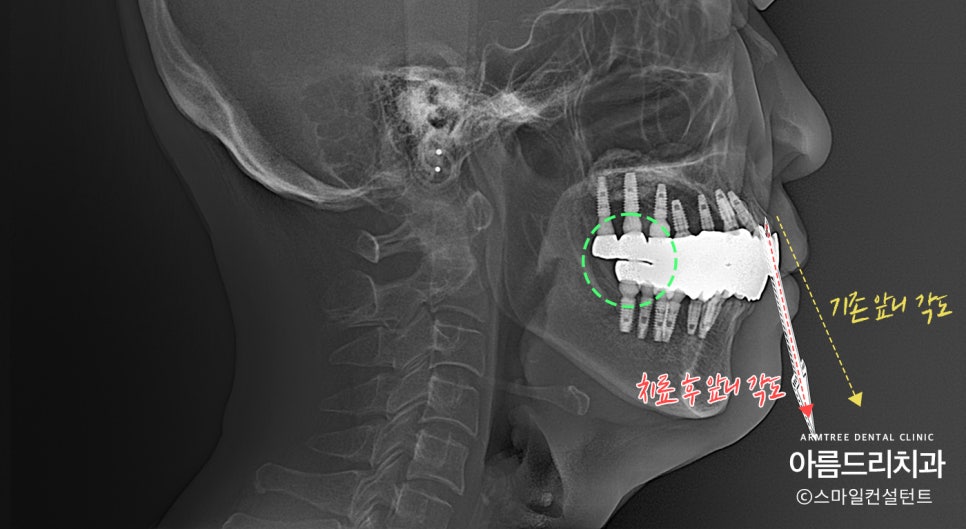

앞니 각도를 줄여서 입이 들어가도록 했습니다.

어금니 교합을 맞춰서 밥이 잘 씹히도록 했으며,

얼굴 길이를 살짝 줄이고 앞니 각도를 조절해서

입술이 편하게 다물어지도록 치료 하였습니다.

연세가 좀 있기 때문에 얼굴 길이를 너무 많이 줄이면

볼살이 쳐저 보일 수 있어서 살짝만 줄였습니다.

임플란트 갯수는 굳이 빠진 치아에

전부 다 심을 필요가 없습니다.

꼭 필요한 위치만 골라서 최소한의 갯수만

식립해야 환자 입장에서도 부담이 없습니다!